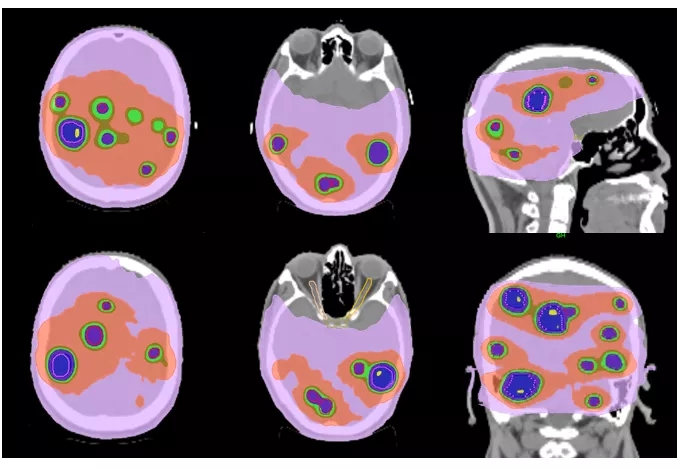

4)治疗范围广,各类肿瘤,均可选择。由于托姆刀的特殊设计和功能,可以治疗位于身体任何部位的肿瘤。

①胶质瘤、脑转移瘤、脑膜瘤等颅内良恶性肿瘤